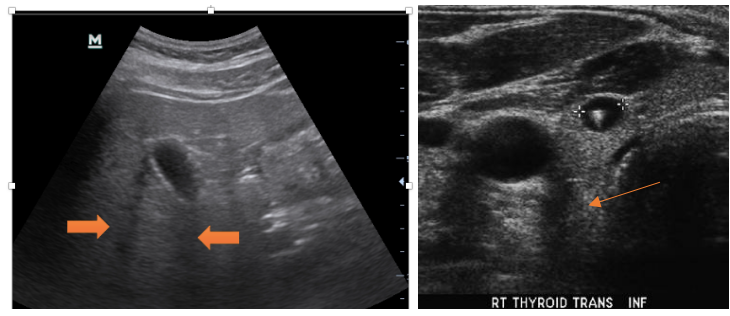

• Echogenicity (超音波反射越多、 影像越亮)

1. Hyper-echoic (亮亮、 白白): air, bone

1. Hypo-echoic (暗暗、 黑黑): fluid ex. water、 blood、 ascites、 abscess

• Posterior enhancement: 因為超聲波全部都穿透, 所以fluid後方的顯影很好

1. Iso-echoic (灰灰): liver, kidney or muscle

1. Posterior acoustic enhancement : 穿過液體後、超音波無減弱、回聲加強

-> 成像變亮, 常見: 膽囊、 膀胱、 心臟、 水泡